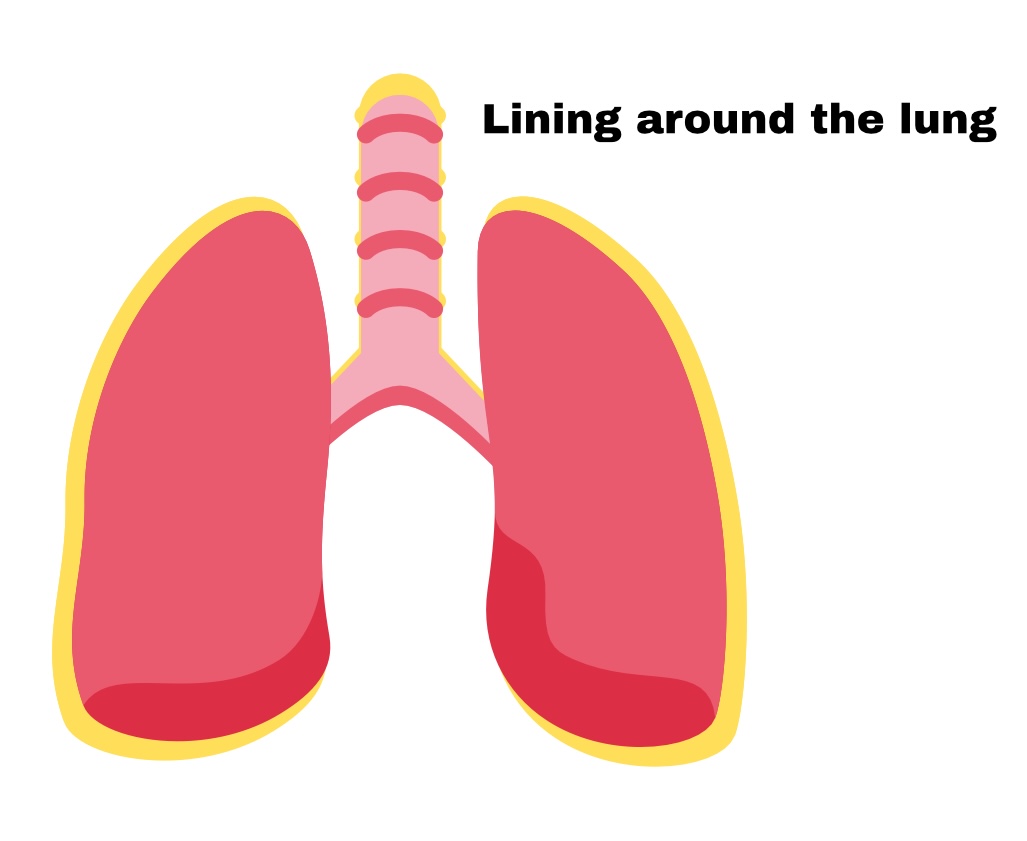

The Lungs=

Pleura

Pleura

membrane around lungs

Partial pleura

Outer layer

Visceral pleura

Deep layer (surface of organ)